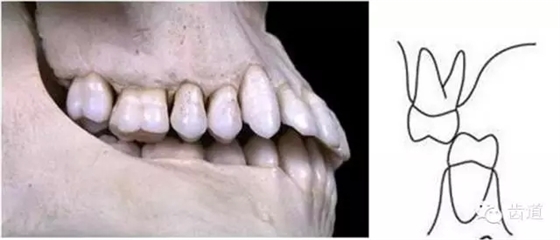

上下牙列間存在著覆蓋、覆牙合

覆蓋Overjet (the horizontal overlap)

覆牙合Overbite (the vertical overlap)

覆蓋(over jet,即超牙合):水平距離

覆牙合(over bite):垂直距離

覆牙合、覆蓋生理意義

a.保護唇頰舌軟組織

b.提高咀嚼效率